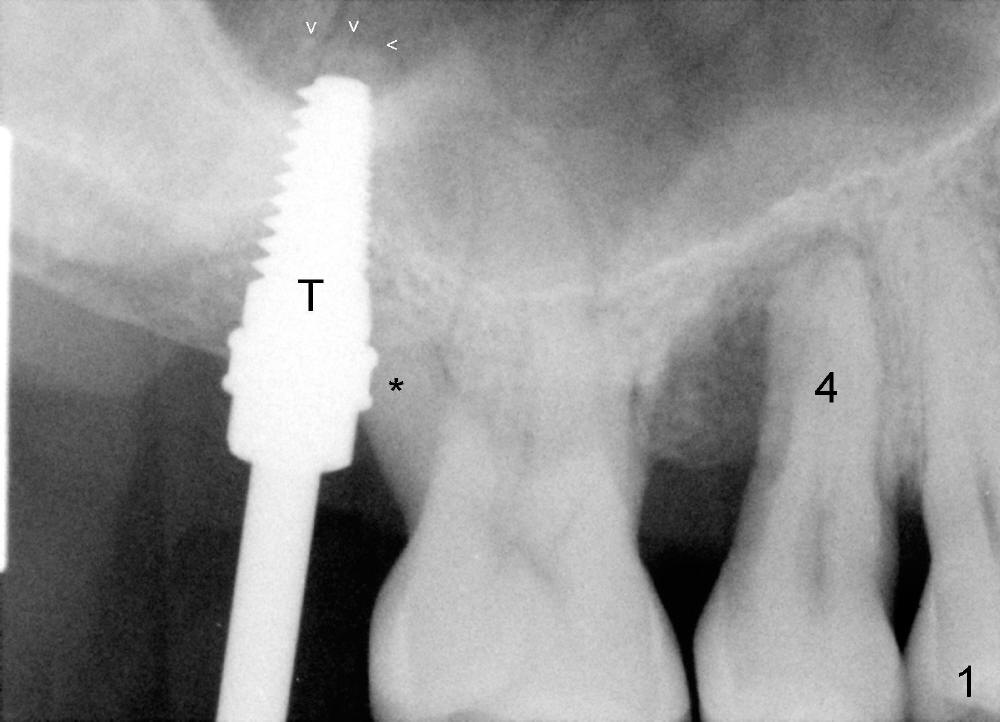

Mr. Kong is 43 years old. He has perio disease, for example #4 (Fig.1). The bone loss may be related to traumatic occlusion. The teeth #2, 14, and 15 are missing. Our primary goal is to restore these missing teeth as soon as possible. The bone height at the site of #2 is 5.8 mm. The Hounsfield units in the oral cortex, medullary and sinus floor are 400, 200 and 500, respectively. A trephine bur with outer diameter of 4 mm was used to start osteotomy (1,2). Probably due to limited access and dense bone, the trephine bur penetrated bone approximately 2 mm. A 2 mm pilot drill was used for further penetration, followed by 2.5-4.0 mm Bicon reamers for cylindrical osteotomy. A 4.5x11 mm tapered tap was used for bone expansion and sinus lift, followed by 5x11 mm tap (Fig.1). At higher magnification, it appears that the sinus floor had been lifted (Fig.1': *). A six by eleven mm tap was used. The apical end of the osteotomy felt to be intact and solid with a slender surgical curette. There was no sign of sinus membrane perforation, as confirmed by nasal blowing test. Harvested bone (from trephine bur and reamers) was pushed as apical as possible. A 6x11 mm implant was placed (Fig.2). It seems that taps/implant-related sinus lift increases the bone height to about 8 mm (Fig.2'). The thread portion of the implant is 6 mm. It appears that the 5x11 mm tap (Fig.1) and the 6x11 mm implant (Fig.2) invade the distobuccal apex of the first molar (*). Clinically there was some distance between them. Preop CT (axial section) may show the point (Fig.3: red circle stands for the implant; *: distobuccal apex of the first molar). The patient returns to office for follow up 1 week postop. The wound is healing normally around the stable implant. There is no percussion tenderness of the tooth #3. No bone resorption is observed 5.5 months postop (Fig.4), 7 months (Fig.5, Jan, 2015), 3.5 years (Fig.6) or 5 years 1 month (Fig.7) post cementation. At #14, bone height is 1-2 mm. Implant placement with sinus graft fails.